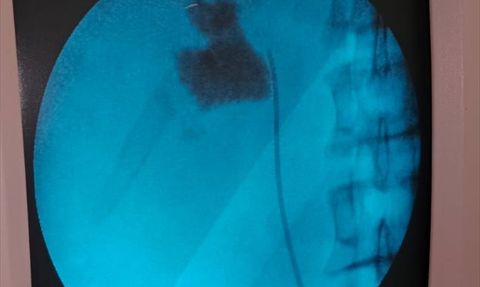

Eskişehir'de Kalp Delik Tedavisi Başarıyla Tamamlandı